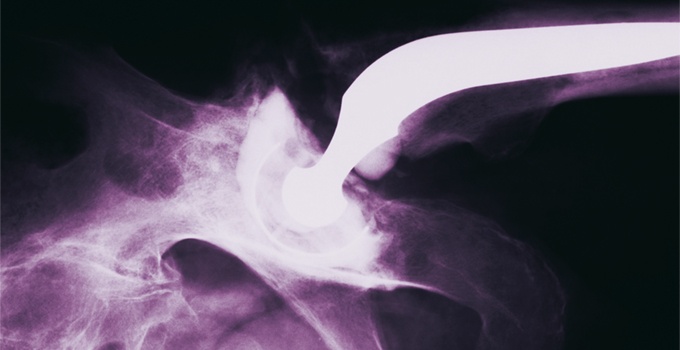

Le diagnostic est confirmé par les radiographies standard avec cliché de face et un faux profil permettant une étude comparative. L’atteinte est volontiers bilatérale et peut être asymptomatique. Une échographie montre un éventuel épanchement articulaire. L’IRM est réservée à l’élimination d’un diagnostic différentiel ou en cas de doute diagnostique. Les clichés standard pourront être répétés en cas d’aggravation et montrer une évolution du pincement, pouvant réaliser une coxarthrose destructrice rapide, ce qui peut se rencontrer notamment en cas de chondrocalcinose. Le bilan biologique est normal et notamment il n’y a pas de syndrome inflammatoire.

Une prothèse totale de hanche (PTH) ne sera pas mise en place avant l’âge de 60 ans, sauf cas particulier. Grâce aux progrès techniques, la durée moyenne de vie d’une prothèse est de vingt ans. Toutefois, le risque d’une usure prématurée ou d’un descellement n’est pas à exclure et pose alors le problème de la reprise chirurgicale, toujours délicate. Trois matériaux constituent les prothèses : métal, polyéthylène, céramique. Ils en limitent l’usure, améliorent la fixation à l’os et évitent la luxation. Actuellement, la voie antérieure mini-invasive est souvent utilisée car elle évite la section musculaire, facilite la mobilisation rapide et réduit le temps de la rééducation fonctionnelle.